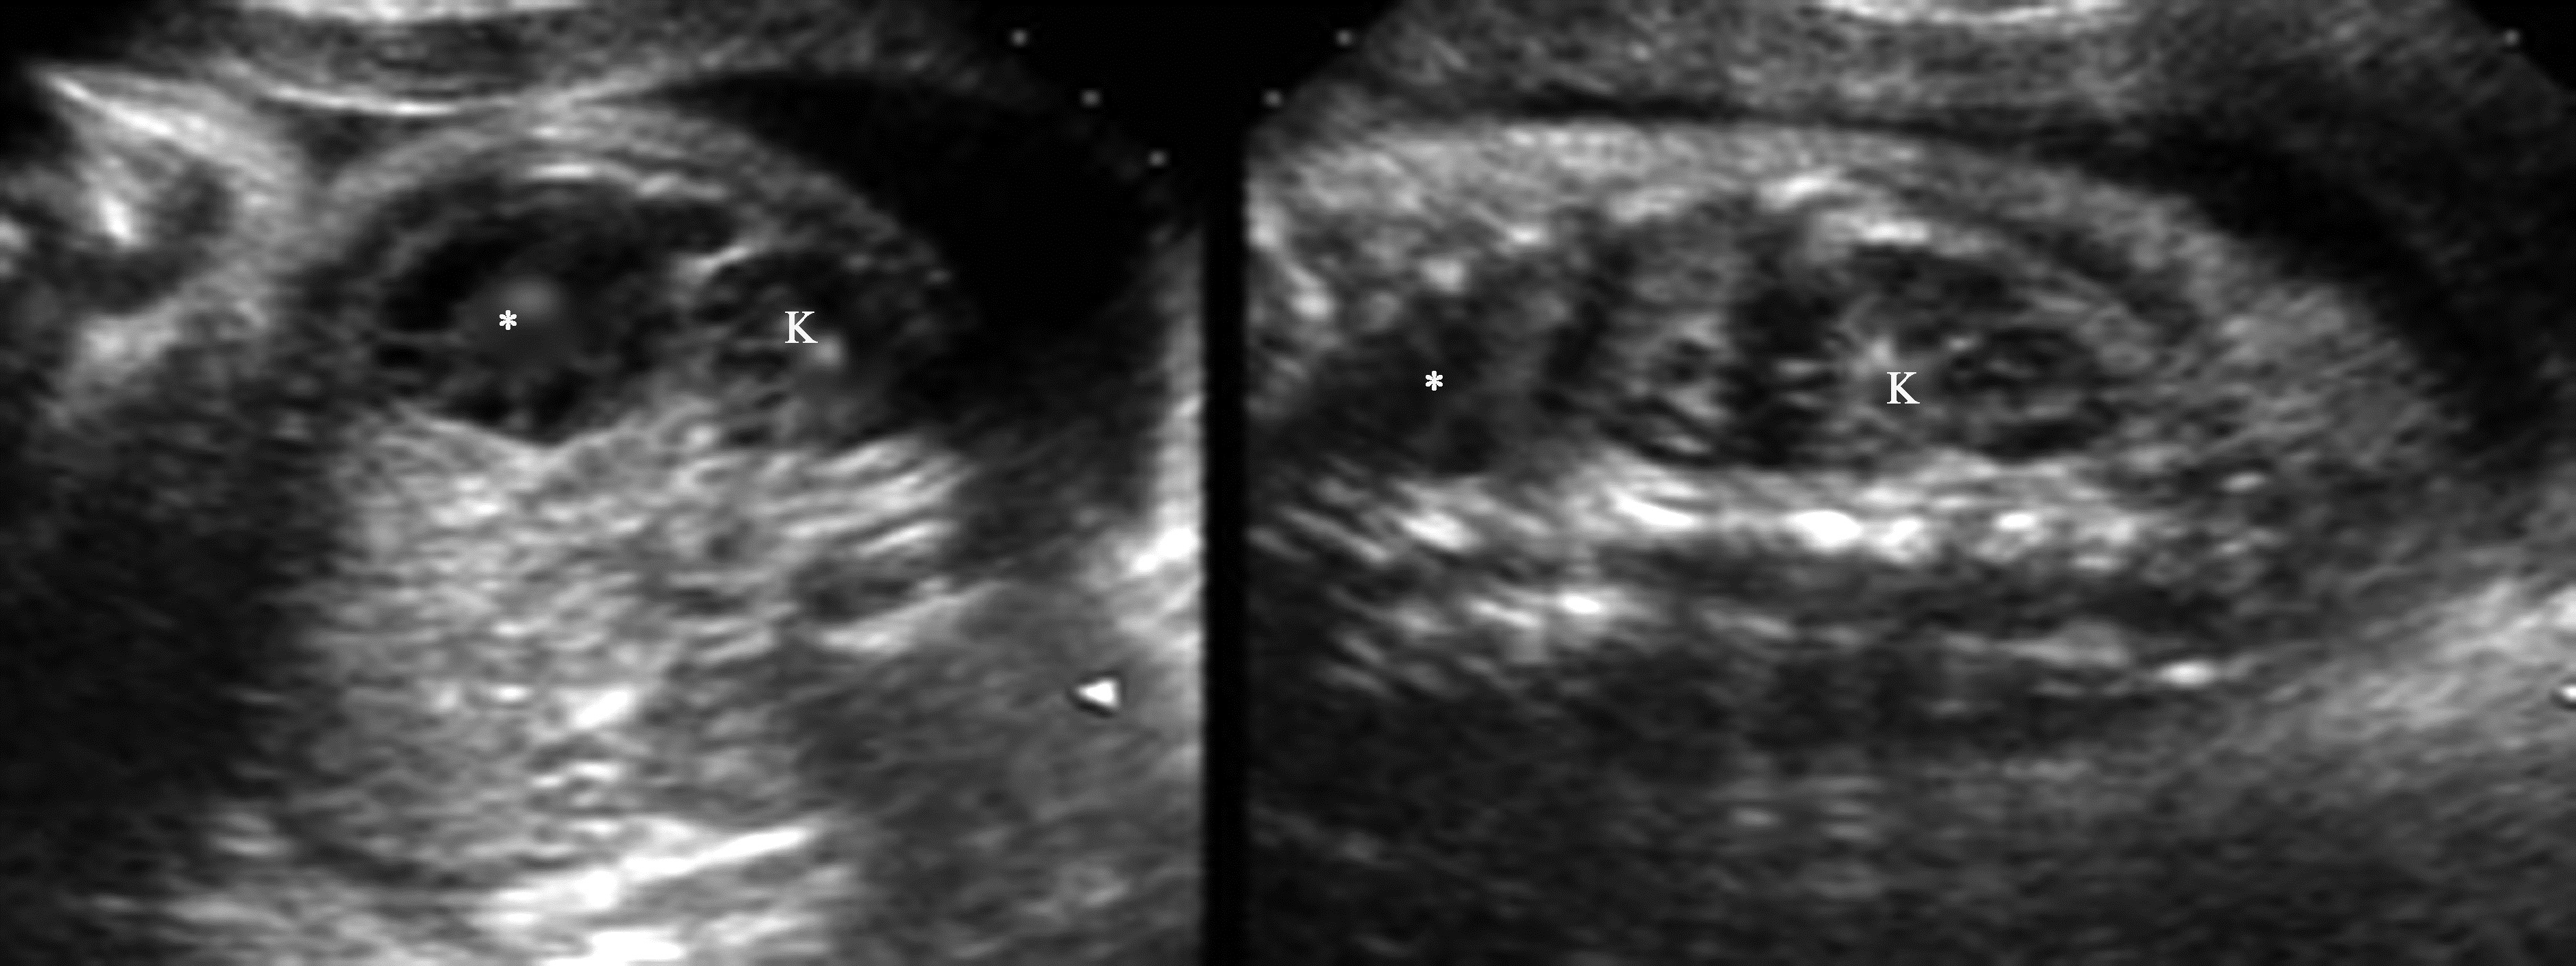

胎儿肿块在孕20周时较少发现,而到孕28周以后就相对多见了,主要原因是各器官在此时期已发育成熟。晚期妊娠是发现胎儿腹部肿瘤的主要时期,胎儿时期肾上腺及肾上极出现的肿块最多见的是神经母细胞瘤,其次是肾上腺出血、肺叶外的孤立肺、支气管源性囊肿、肾发育不全等,但此时期发现的神经母细胞瘤既可以是实质性,也可以是囊实性或囊性,因此除手术外常较难进行有效鉴别诊断。由于胎儿时期发现的神经母细胞瘤通常在生后时处于Ⅰ、Ⅱ或Ⅳ~S期,很多文献报道预后良好。胎儿肾上腺区肿块(图1)不论是良性病变或是恶性肿瘤,预后多良好,但需要生后严密视察随访。肾脏肿瘤罕见,常见的是肾中胚层瘤,位于胎儿肾内,较大,回声均匀,边界较清楚,可压迫肠管,其内彩色血流信号丰富,常伴羊水过多,生后手术成功率高,预后好。胎儿肾脏Wilms瘤很少见。

图1 孕29周胎儿左肾上腺区肿块(*)声像图